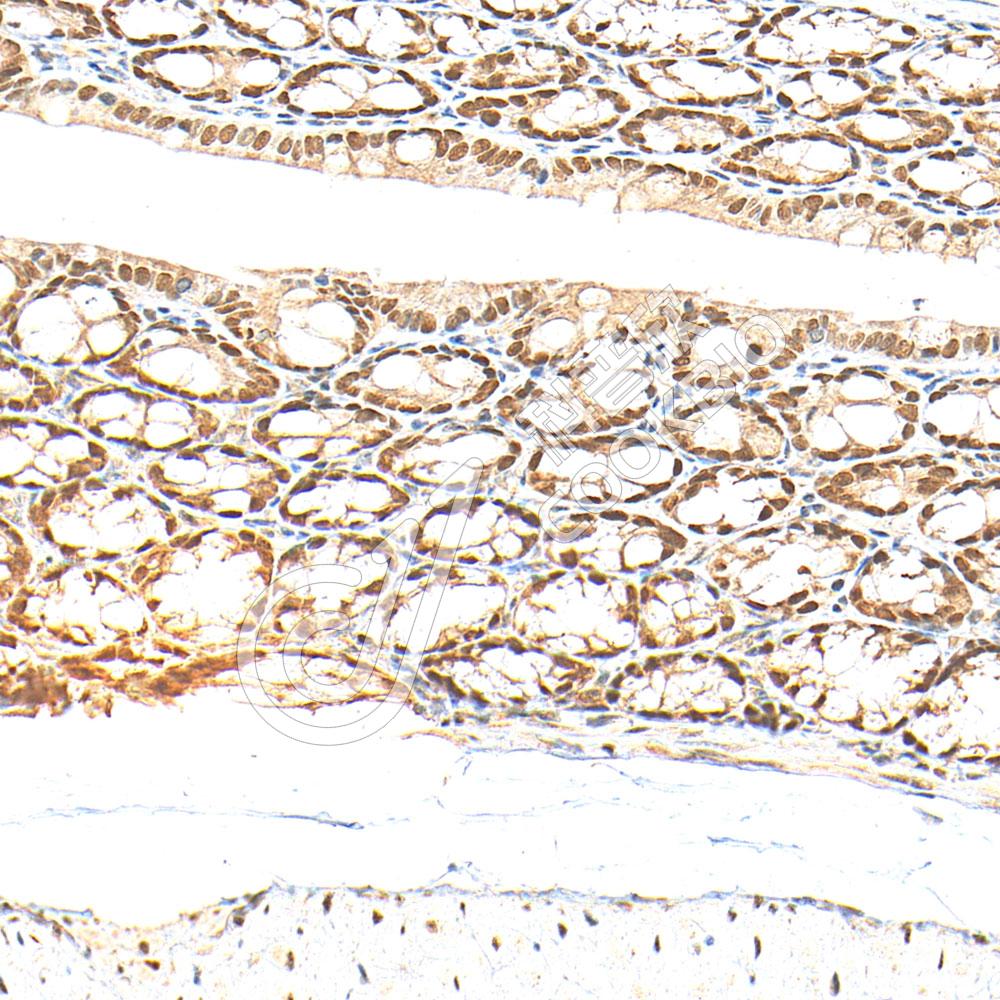

IHC检测CDX2蛋白(货号 K5454503).

样品: 小鼠结肠, 4%多聚甲醛 (货号KSG1101) 固定12-24小时.

抗原修复: 柠檬酸抗原修复液(干粉, pH 6.0) (KSG1201), 高压锅均匀喷气计时2分钟.

—抗: 1: 1300稀释, 4℃ 孵育过夜.

二抗: S-vision免疫组化多聚二抗(山羊抗小鼠), 即用型(货号KB3903), 室温孵育20分钟.